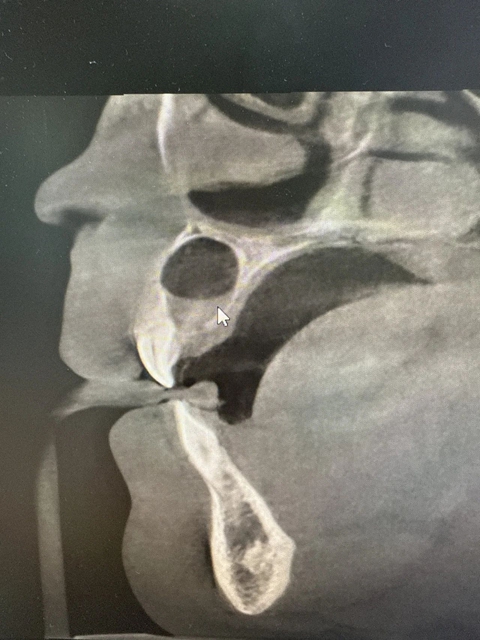

术前

术后